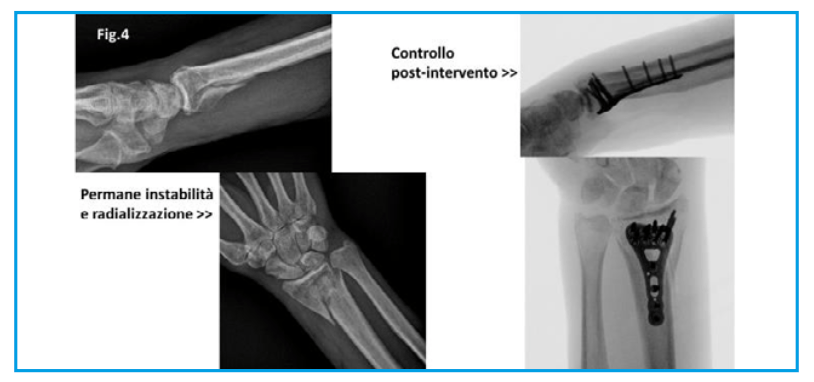

Indicazione chirurgica: intervento di revisione chirurgica con via di accesso secondo Henry, asportazione del callo osseo riparativo, riduzione della neo-frattura e stabilizzazione con placca in titanio nickel-free a basso profilo.

In considerazione della ottima stabilizzazione, si lascia libera da subito l’articolazione per un inizio precoce della riabilitazione. Un tutore termoplastico sarà, poi, posizionato per essere usato nei momenti di maggior stress e rischio (attività lavorativa e durante la notte).

Operato al 45° giorno; viene sottoposto ad intervento di asportazione del callo osseo riparativo, riduzione della neo-frattura e osteosintesi con placca a basso profilo in titanio nickel-free con raggiungimento di un ideale allineamento anatomico.

Nessuna indicazione per gesso nel post-operatorio, solo bendaggio elastico non adesivo e inizio immediato delle mobilizzazione.